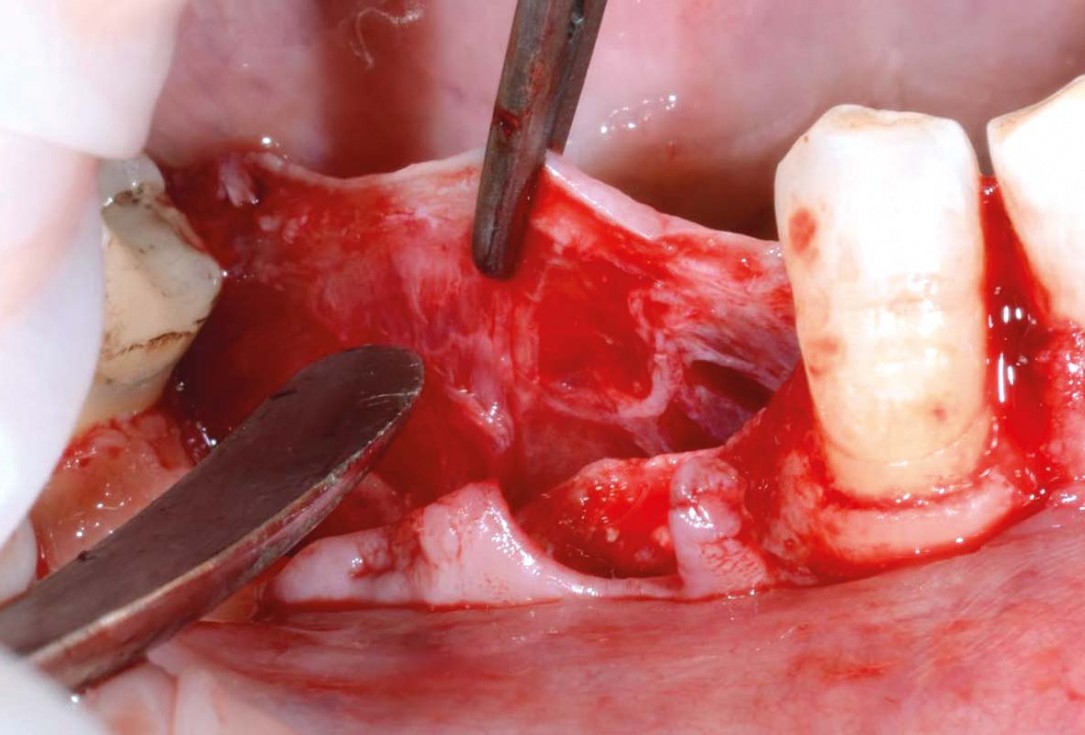

04/29 - Clinical view after exposure of the defect, to promote healing the local bone was perforatedVertical bone augmentation and broadening of attached gingiva using cerabone®, permamem® and mucoderm® - Dr. R. Naimoli